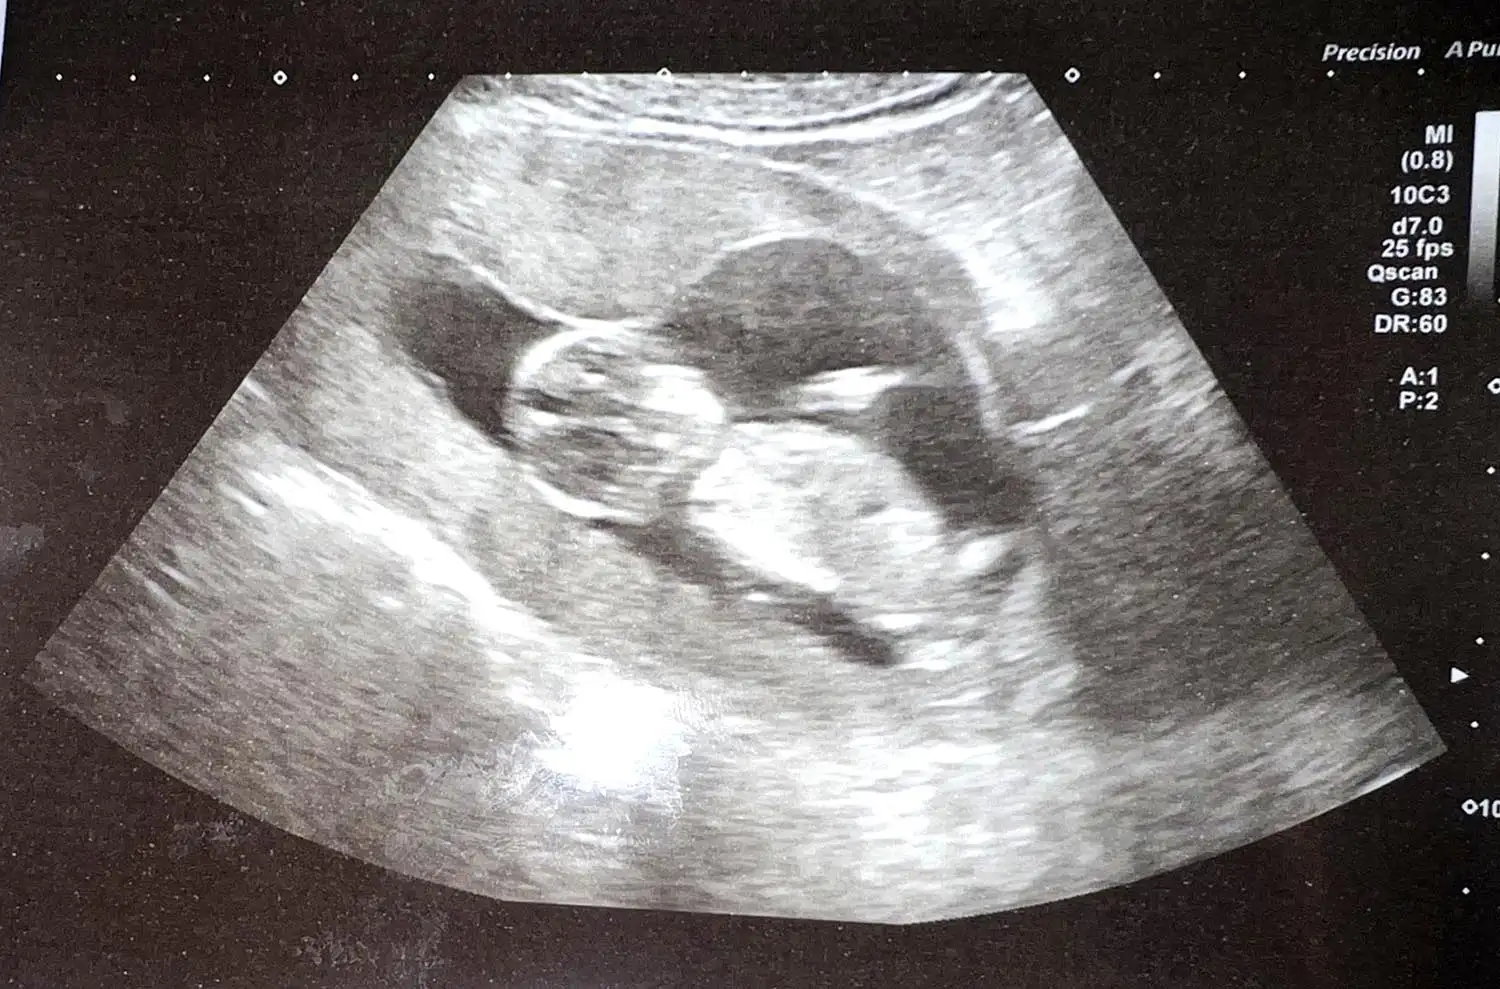

Sophia was rushed to the local hospital, where doctors initially suspected she had pneumonia. However, scans and a biopsy revealed that she had a tumor over her heart. She was diagnosed with pre-mediastinal large B-cell non-Hodgkin’s lymphoma — a type of cancer that affects the lymphatic system — in September 2024.